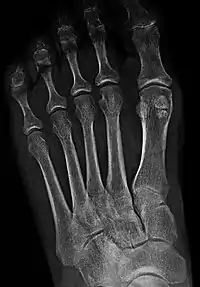

Los sesamoideos del pie, actuando como polea para los tendones, ayudan a que el primer dedo del pie se mueva normalmente y proporcione una acción de palanca, cuando el dedo gordo “empuja” al caminar y correr. También sirven como una superficie que soporta el peso para el primer hueso metatarsiano (el hueso largo que se conecta con el dedo gordo del pie), absorbiendo el peso que se aplica en la bola del pie al caminar, correr y saltar.

- Articulación metatarsofalángica.

- Articulación del primer y segundo dedo o entre el tercer y el cuarto.

- Articulación interfalángica de dedo gordo.